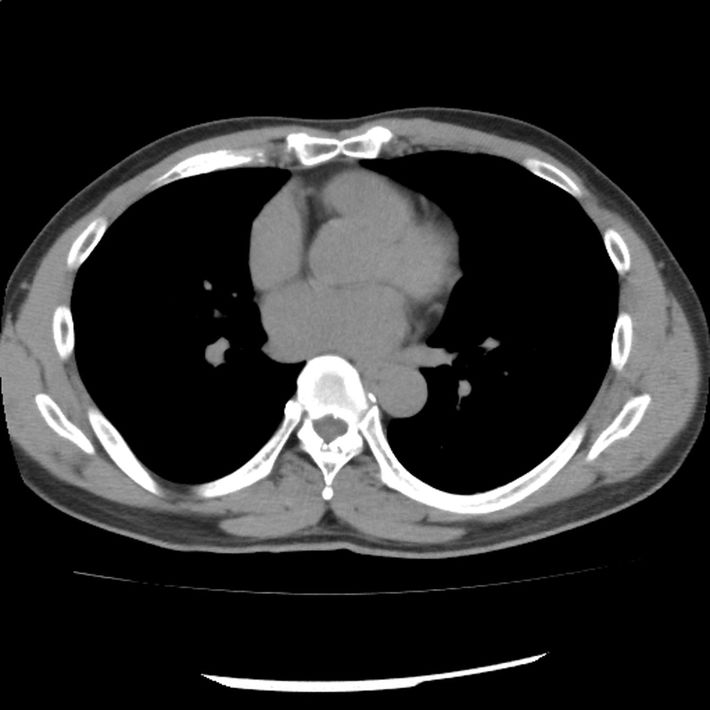

肺がん検診の「異常なし」を信じてはいけない…「もう手術はできない」と宣告され、7年闘病した40代男性の後悔

【画像1】「異常なし」と記載された検査報告書

胸部を輪切り状に撮影したCT画像のひとつ(*患者本人の掲載許諾済み)